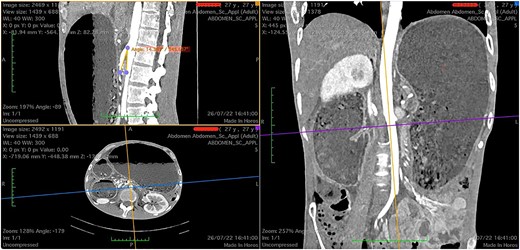

There was extrinsic compression of third portion of the duodenum by the SMA (Fig. 2).

Computed tomography axial section showing a dilated stomach resulting from compression of third portion of duodenum.